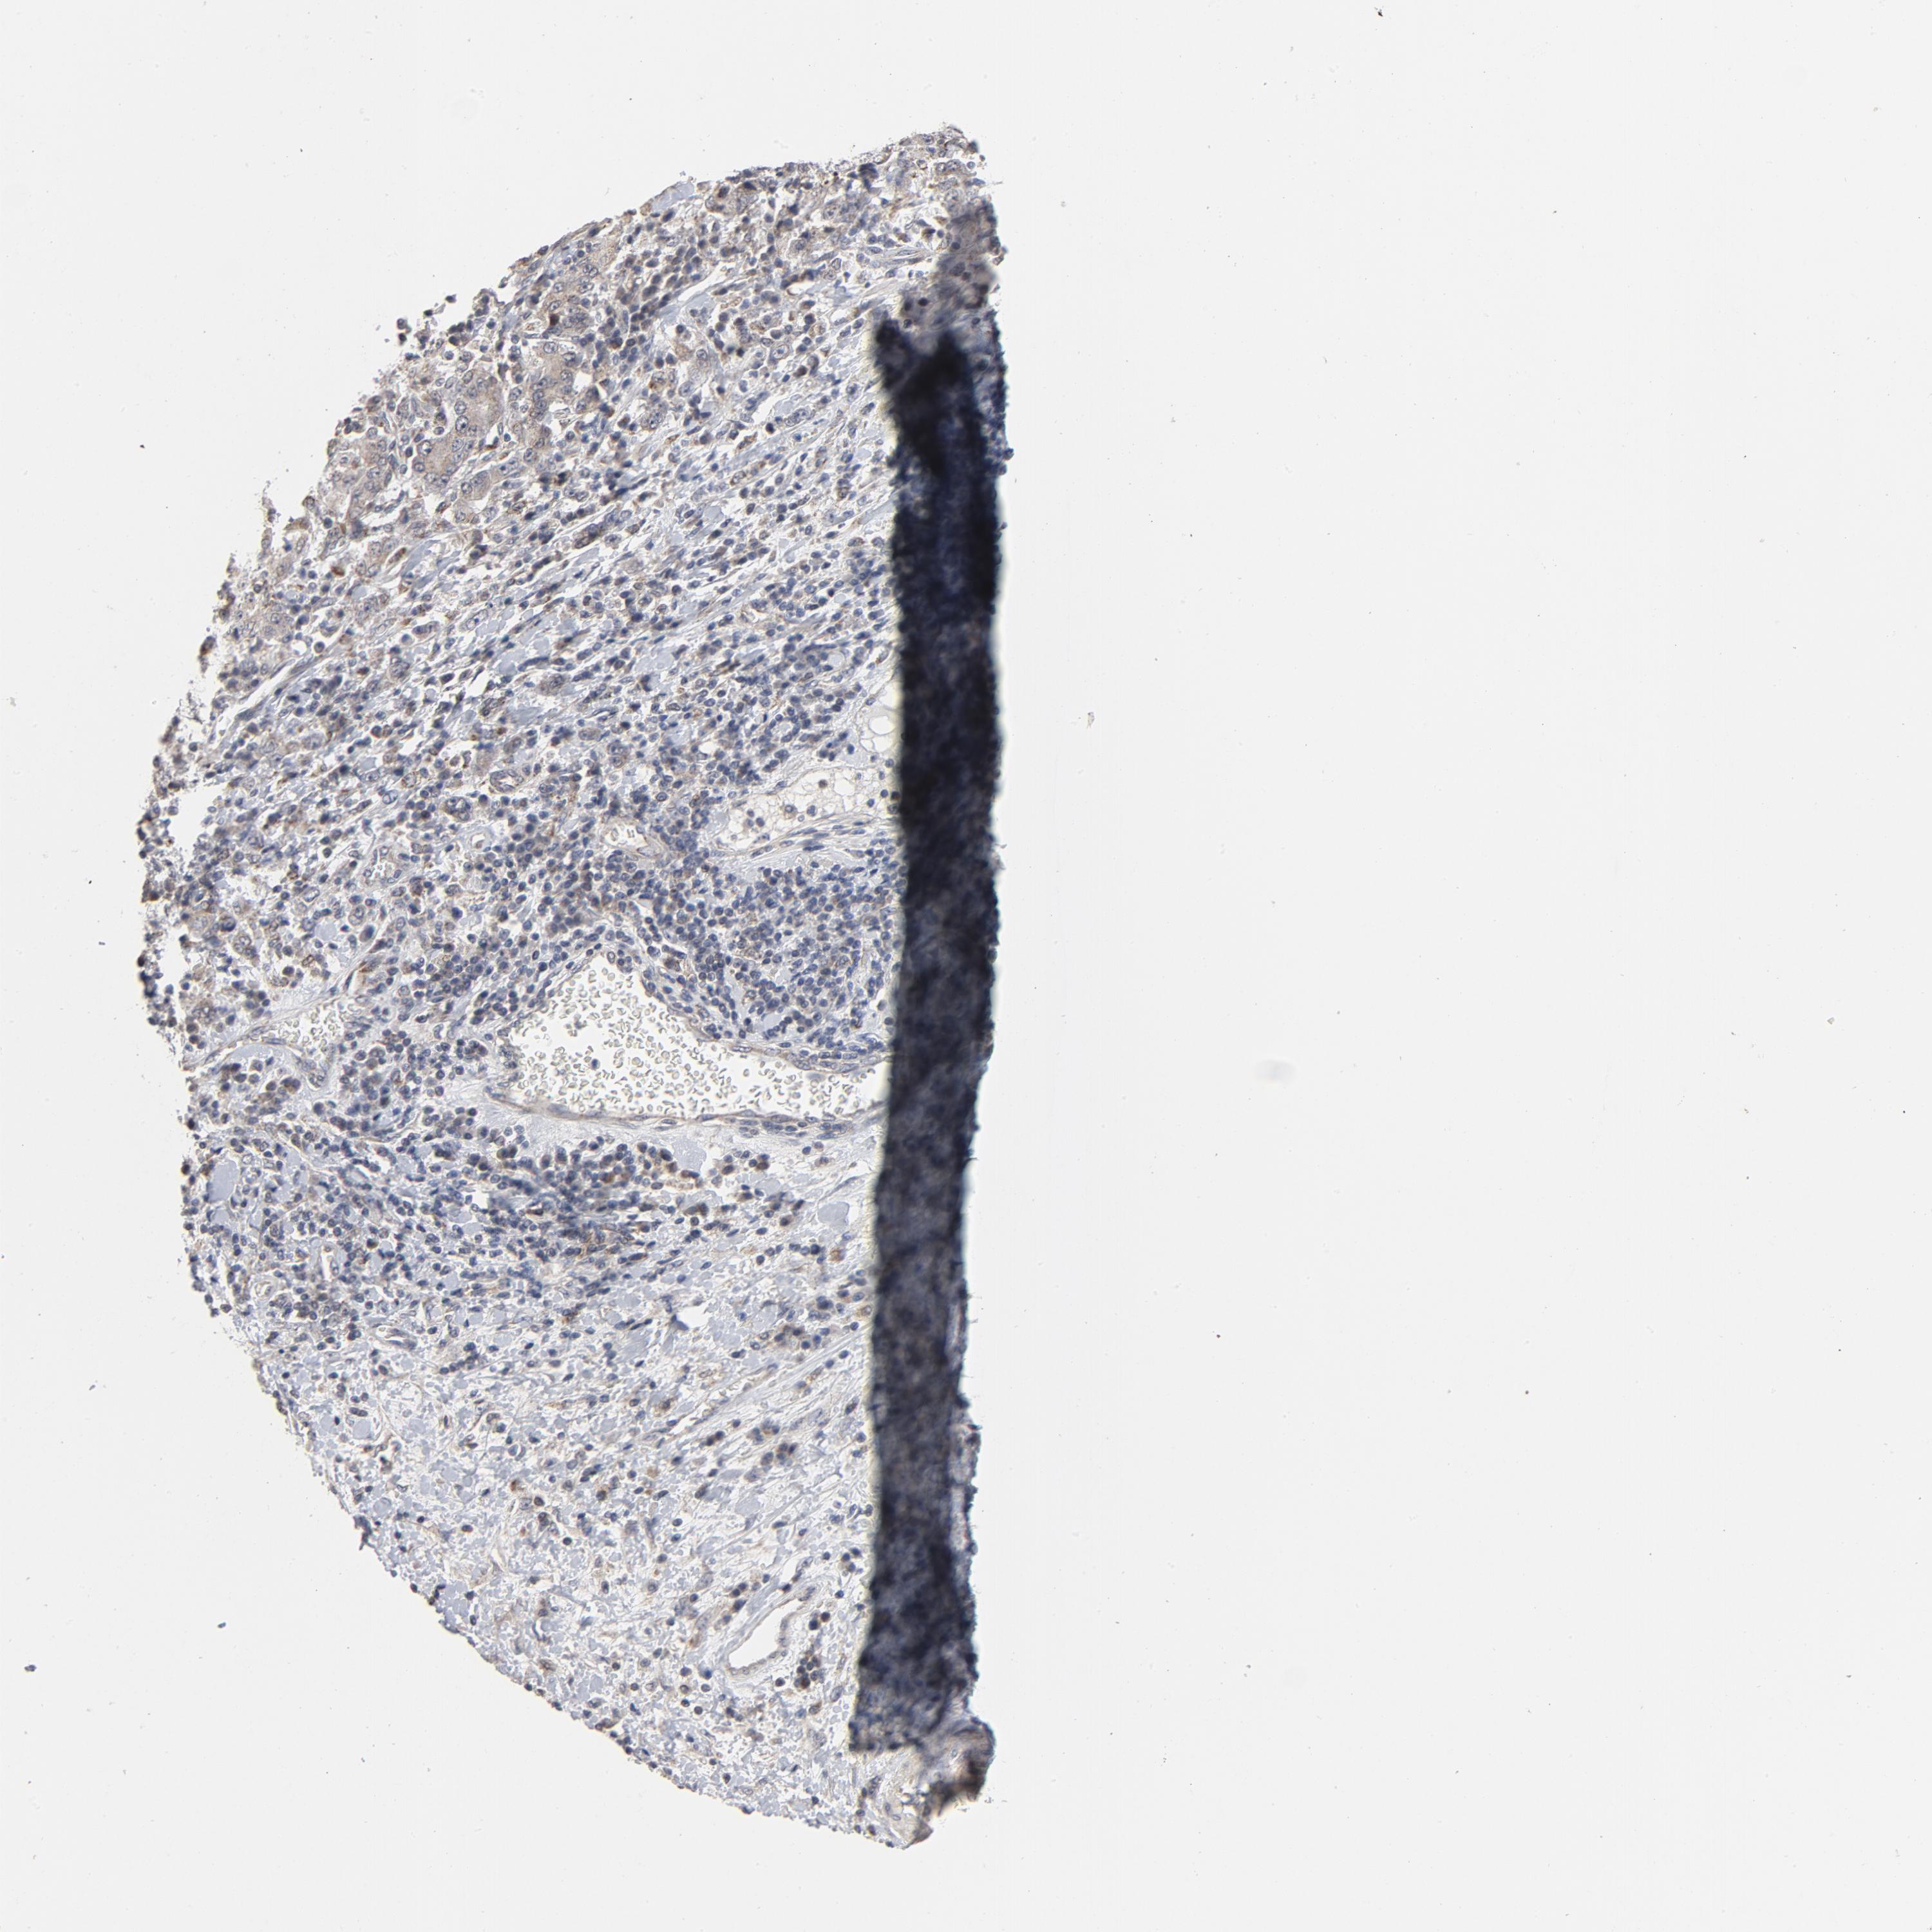

STOMACH CANCER - Protein expressioni

A mouse-over function shows sample information and annotation data. Click on an image to view it in a full screen mode. Samples can be filtered based on level of antibody staining by selecting one or several of the following categories: high, medium, low and not detected. The assay and annotation is described here.

Note that samples used for immunohistochemistry by the Human Protein Atlas do not correspond to samples in the TCGA dataset.

Antibody stainingi

Antibody staining in the annotated cell types in the current human tissue is reported as not detected, low, medium, or high, based on conventional immunohistochemistry profiling in selected tissues. This score is based on the combination of the staining intensity and fraction of stained cells.

Each image is clickable and will lead to virtual microscopy that enables deeper exploration of all samples and also displays staining intensity scores, fraction scores and subcellular localization as well as patient and tissue information for each sample.

Antibody HPA048630

Antibody HPA061142

Antibody CAB004026

Staining

High

Medium

Low

Not detected

Intensity

Strong

Moderate

Weak

Negative

Quantity

>75%

75%-25%

<25%

None

Location

Nuclear

Cytoplasmic/membranous

Cytoplasmic/membranous,nuclear

Adenocarcinoma, NOS

Adenocarcinoma, High grade